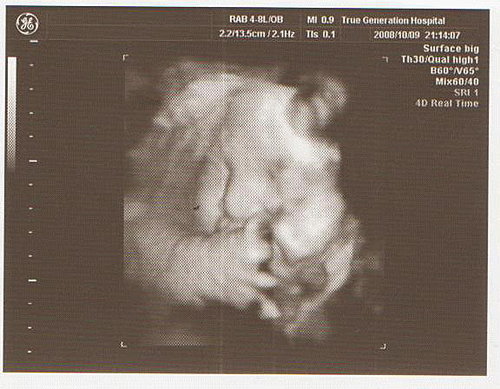

結果今天去產檢

寶寶的體重仍是直線上升

已經3260公克了

整個臉胖嘟嘟的

醫生也說寶寶超重了

生產過程會比較辛苦

如果下週還沒生

再安排胎盤的檢查